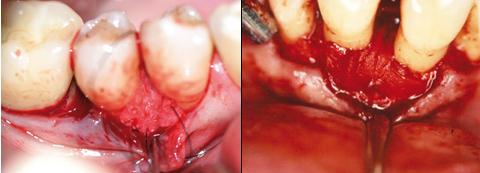

Nach Abschluss der antiinfektiösen Therapie und Sondierung des Limbus alveolaris wird unter Lokalanästhesie mithilfe des mikrochirurgischen Skalpells eine intrasulkuläre Inzision unter maximaler Gewebeschonung vorgenommen. Je breiter der Interdentalraum ist, desto weiter wird nach bukkal inzidiert (Abb. 1). Auf Entlastungsschnitte wird, wenn möglich, verzichtet. Ein Papillenelevator ermöglicht die schonende Darstellung der interdentalen Papille (Abb. 2).

Abb. 1: Intrasulkuläre Inzision ohne Entlastungsschnitte unter maximaler

Gewebeschonung. Abb. 2: Der Papillenelevator ermöglicht die schonende Darstellung der

interdentalen Papille.